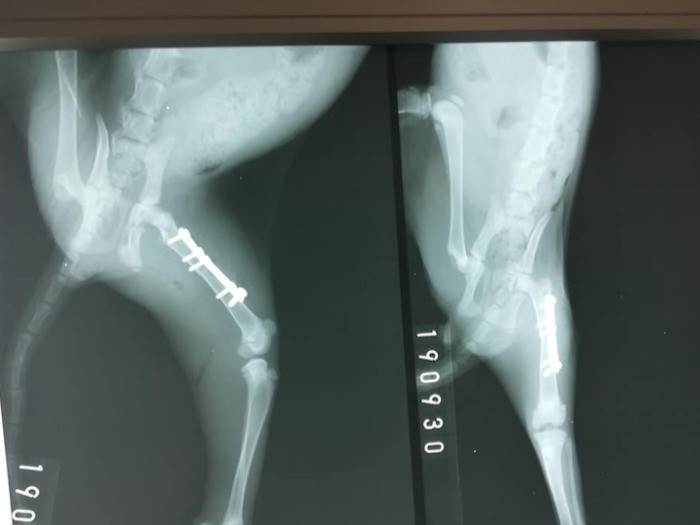

「立てるけど左後ろ脚がふらふらで、病院で診てもらうと、折れていて……。車にひかれたんでしょう。すぐに手術をお願いして、プレートで固定してもらったんです」

ぷぅーちゃんの手術費用は、プレートを外す手術も含めて「ねこかつ」が負担する。2匹はこうして幸運にも命を救われ、カフェで新しい家族が見つかるのを待つこととなった。

「カフェに来た時はガリガリだったからね。2月になったら足のプレートも取れる。そうしたらもっと自由になるからね」